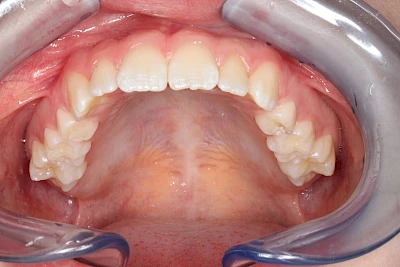

Verfärbungen an Zähnen können außen aufgelagert oder im Zahn eingelagert sein.

Von außen (exogen) eher dunkel gefärbt und meist mehrere Zähne betroffen:

- Durch übermäßige Fluorideinlagerung in der Zahnreifung (mehrere Zähne, weißlich-fleckig)

Gerade bei Kindern und Jugendlichen werden zunehmend häufiger bräunliche Verfärbungen mitunter auch mit Formveränderungen (die Oberfläche ist rauh oder zerklüftet) der Zähne beobachtet. Meist sind Schneidezähne oder Backenzähne betroffen. Dies könnte ein Hinweis auf sogenannte Kreidezähne (MIH: Molaren-Inzisiven-Hypomineralisation) sein.

Bräunliche Verfärbung